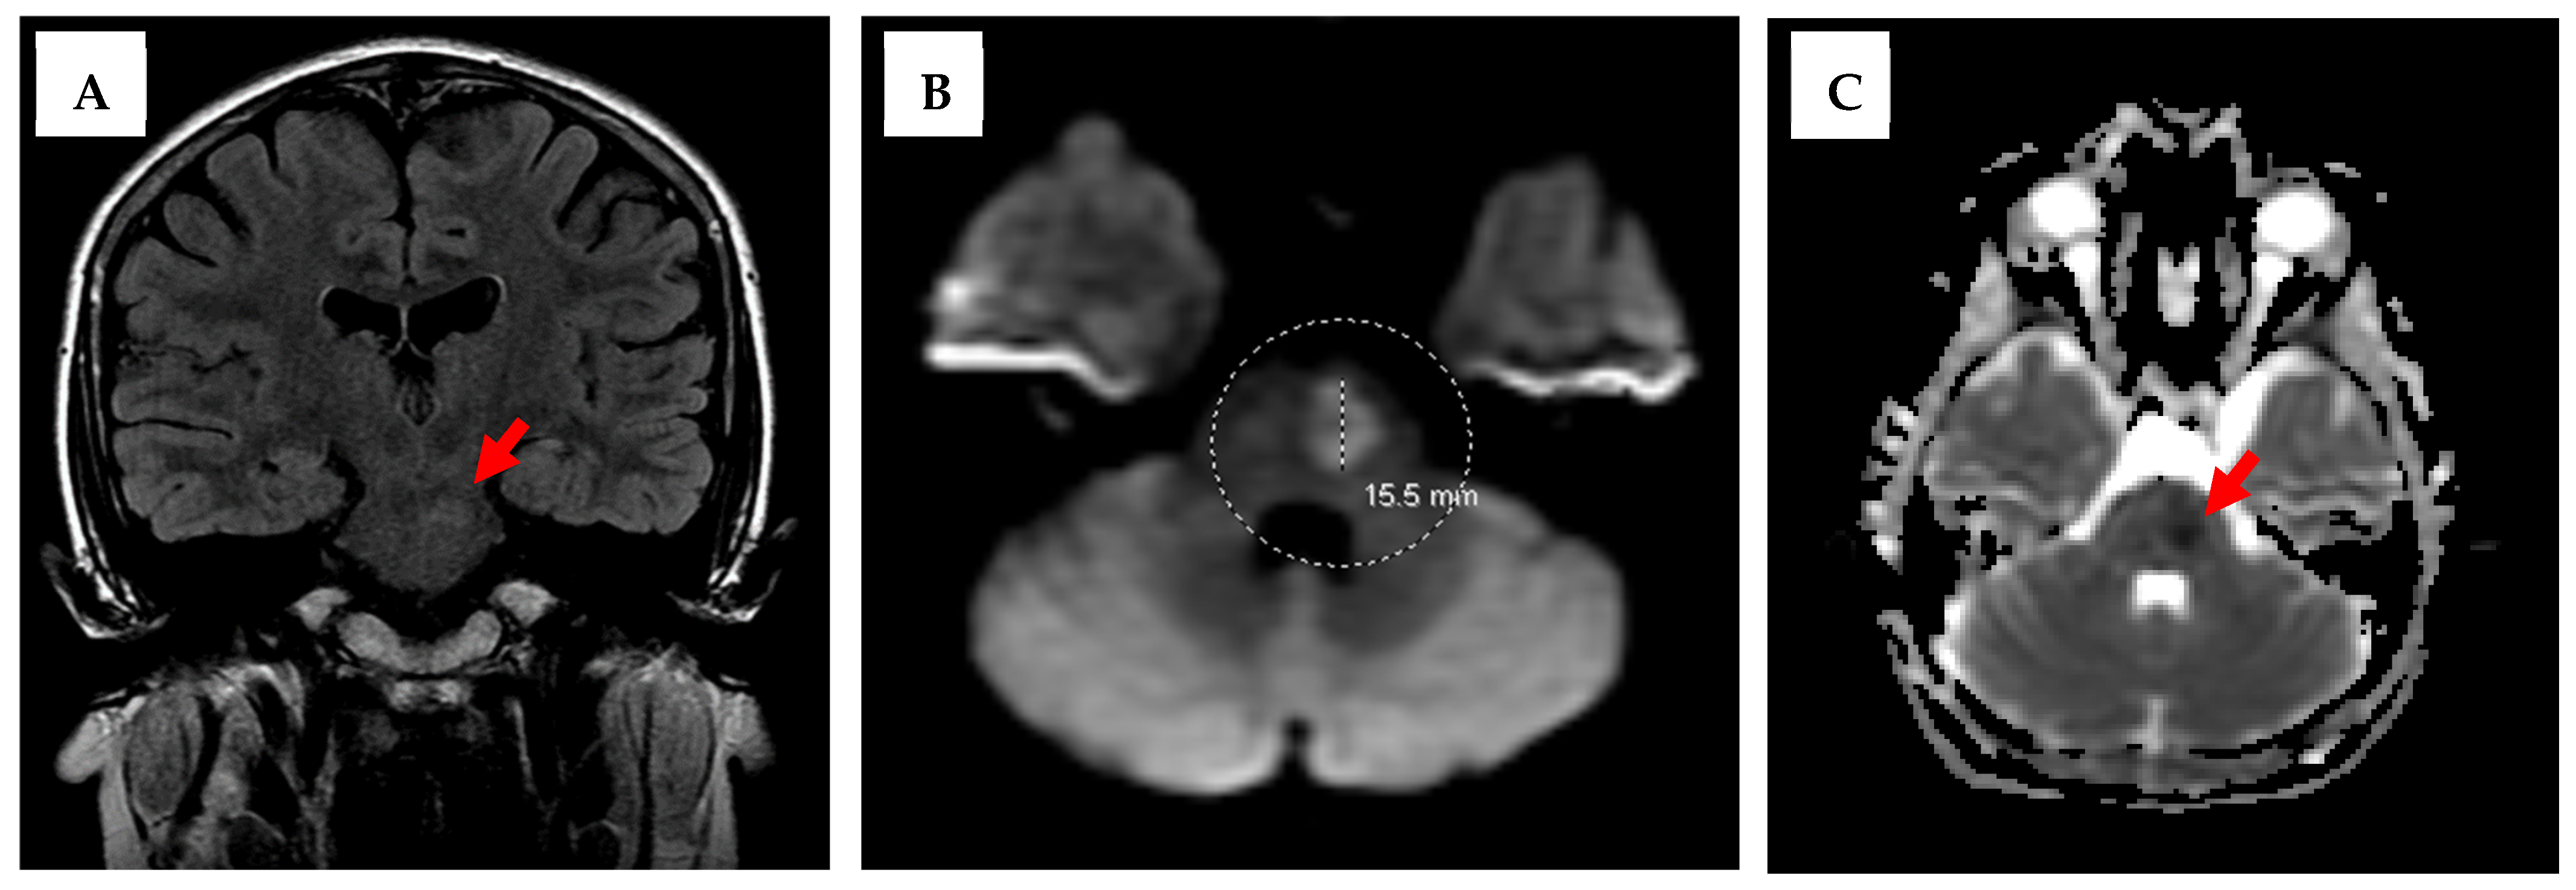

Rare Pediatric Posterior Stroke Case Report with Discussion of Brainstem Lesions

2. Case